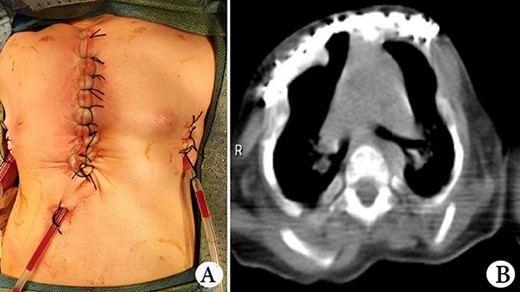

The patient was a female infant born at term with no family history. After birth, the patient developed cyanosis and dyspnea immediately, and emergency intubation and ventilation were performed. One week later, she was weaned and oxygen was given with mask. Oxygen saturation could be maintained basically, but it would decrease when eating and crying. She was eventually diagnosed as ATD and admitted to our hospital to accept surgery four months after birth. Physical examination showed that her chest circumference was 35 cm, and her thorax was narrow and small (Fig. 1A). CT scan revealed that her thorax was deformed, the lateral chest walls were slightly sunken and the lung compression was obvious (Fig. 1B). The operation was performed under general anesthesia. Midsternotomy was made. After the two sternal halves were expanded, three steel bars were placed and fixed on the anterior surface of the sternum (Fig. 2A and B). The bars were covered with pectoralis major muscles, and the skin incision was eventually sutured (Fig. 3A). The chest circumference increased to 40 cm, and the respiratory function was significantly improved postoperatively. Mechanical ventilation was continuously used for 3 days after operation. After weaning, the mask was used for intermittent oxygen supply and stopped 35 days after operation, with the oxygen saturation maintaining above 91%. The patient was discharged 41 days postoperatively. She was followed up for 3 months. There was no hypoxia when calm, but mild hypoxia when crying, which would be relieved after quiet. CT examination 3 months after operation showed that the shape of thorax is improved (Fig. 3B).

(A) Thorax appearance after operation, and (B) CT scan image of thorax after operation.

The reported MTE is to put materials between the two sternal halves, which increase the thorax volume by increasing the circumference [1]. We found that if the space between the sternal halves were not occupied by materials, it would help to increase the thorax volume. Therefore, we put the steel bars on the anterior surface of the sternal halves, leaving the gap in the middle empty (Fig. 2A). This procedure can not only increase the chest circumference but also increase the space between sternal halves. We think that it will help to increase the chest volume.